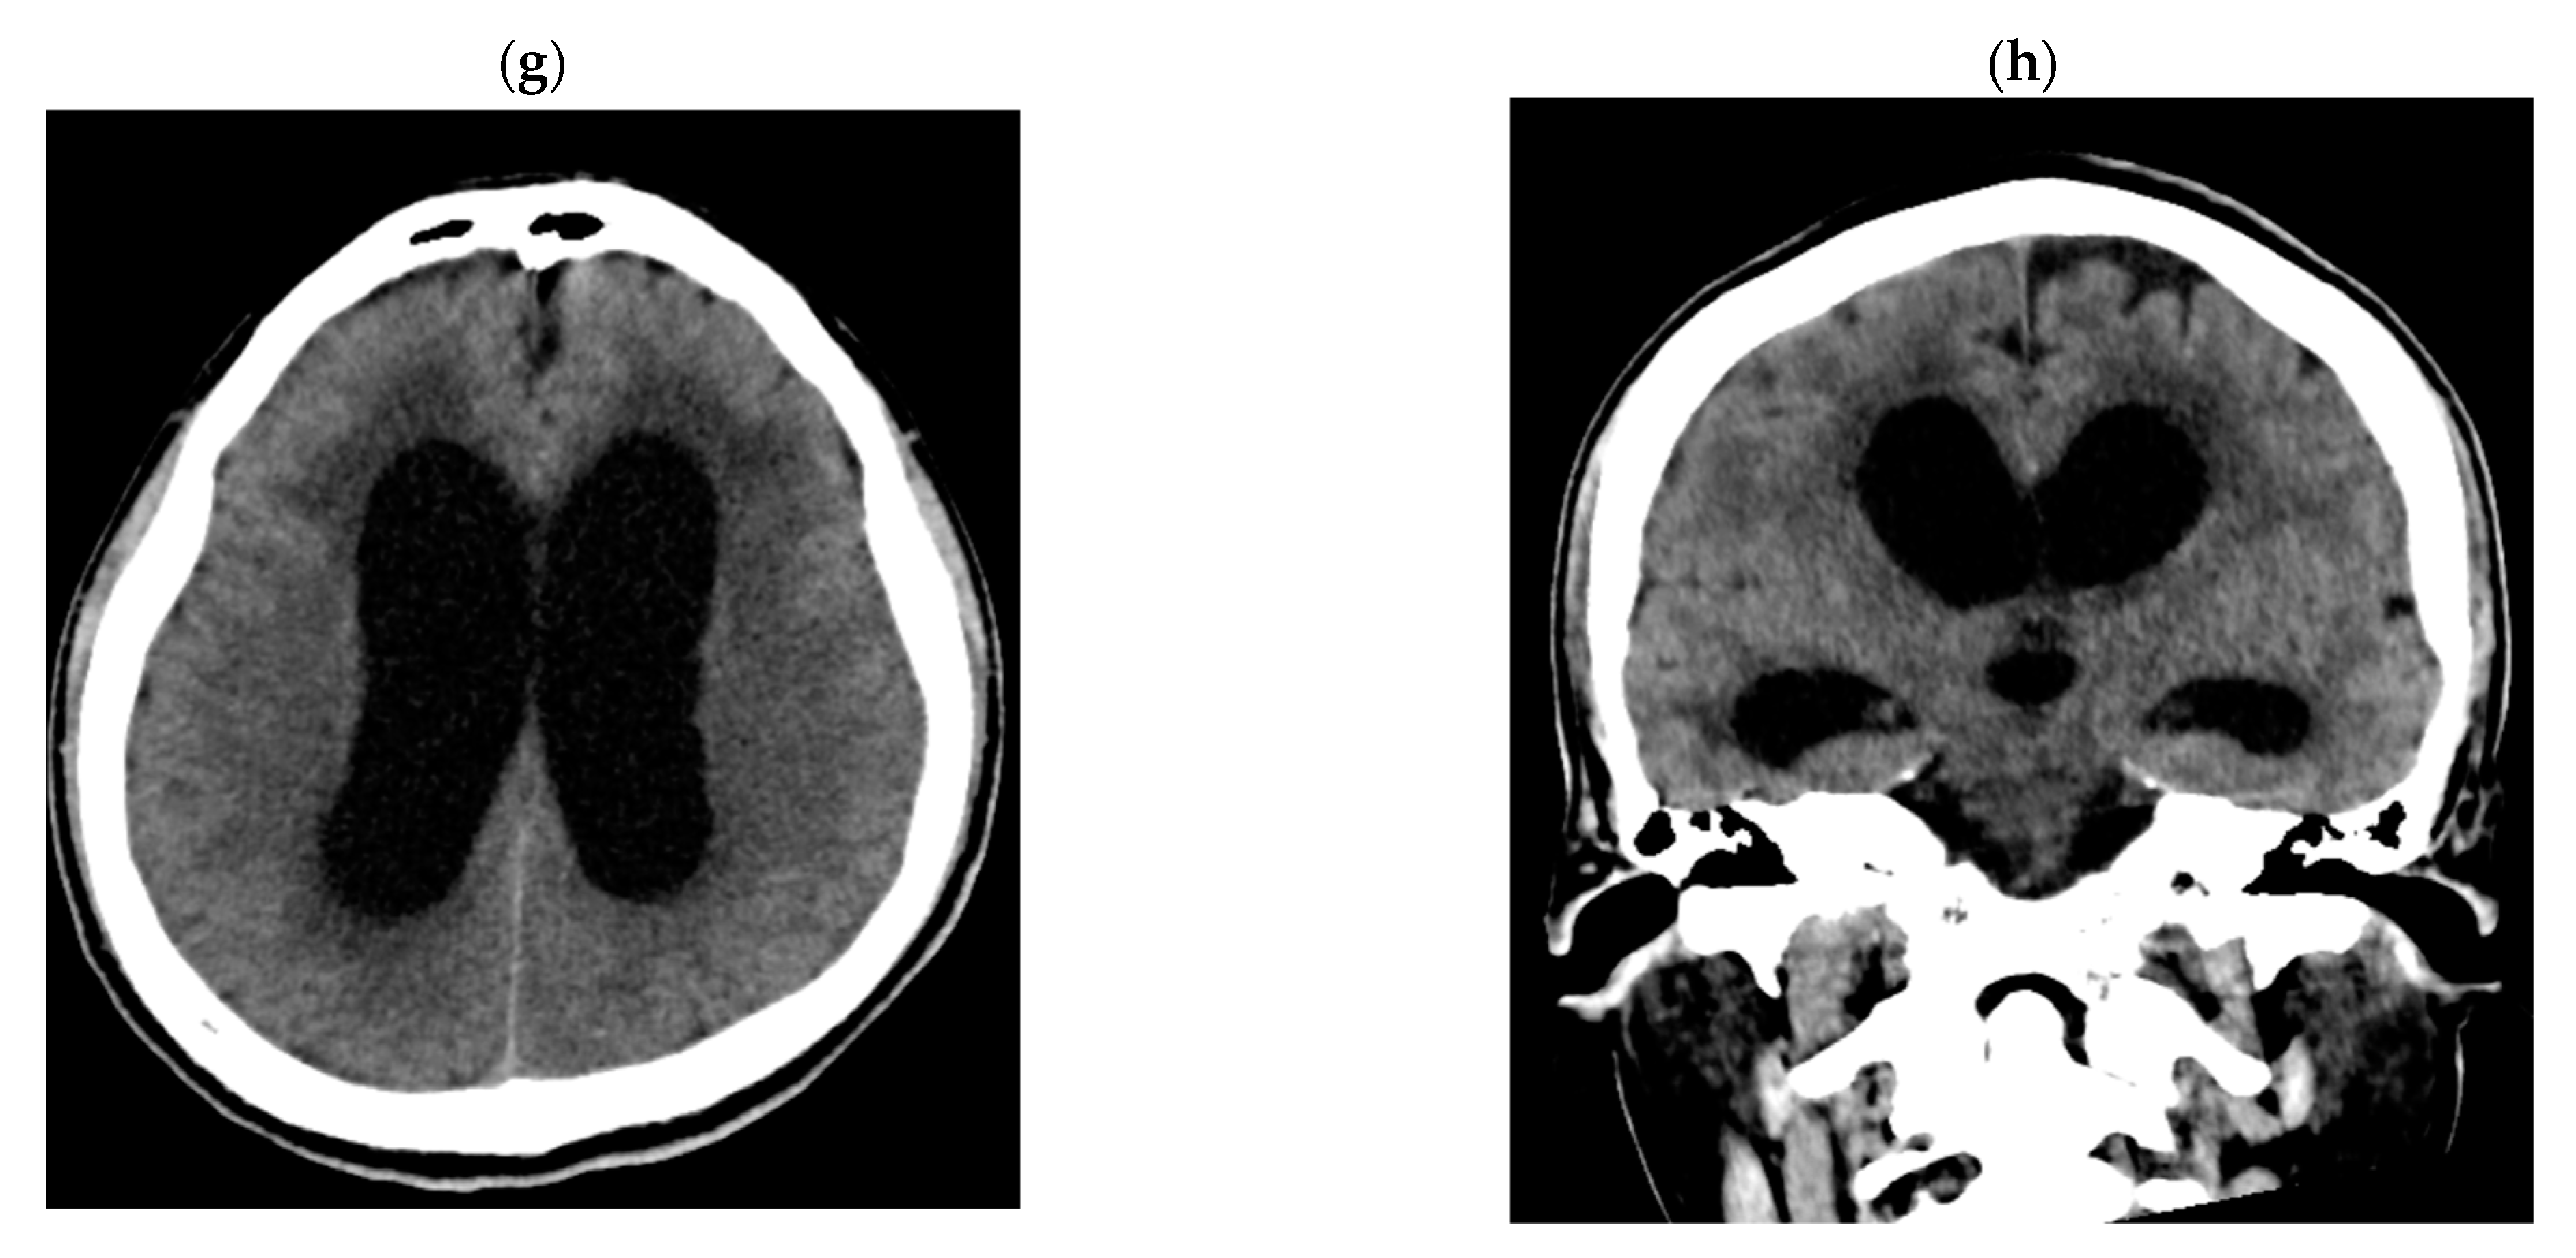

2.2. Detailed Case Descriptions